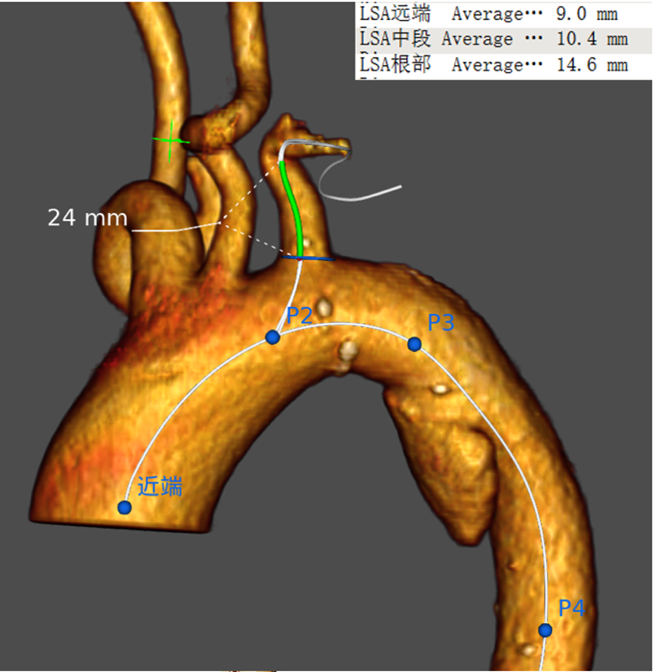

上午的最后一台手术是由江苏省人民医院心脏大血管外科倪布清教授带来的AnkuraTMII支架胸主原位开窗术。患者为41岁男性,于8小时前突发胸背部疼痛,查多排CT胸部平扫CTA示:主动脉弓见双腔影,考虑主动脉夹层(StanfordB型)。既往高血压病史,吸烟史10年,饮酒史10年。倪布清教授团队经过详细测量,决定采取胸主动脉覆膜支架植入+LSA原位开窗重建术。

穿刺右侧股总动脉,置入5Fr短鞘,交换8Fr短鞘,引入0.035软导丝配合5F猪尾导管送至升主动脉,造影提示主动脉夹层,破口距离左锁骨下动脉约1.5cm。穿刺左侧肱动脉,置入10Fr短鞘,软导丝配合猪尾导管送至升主动脉,退出右侧股动脉短鞘,送入34-160mm胸主动脉覆膜支架,至降主动脉,再次造影定位。退出猪尾导管,交换0.035软导丝,送入8Fr可调弯长鞘,于左颈总动脉开口后缘定位释放胸主动脉覆膜支架,经FustarTM可调弯长鞘手推造影显示左锁骨下动脉,将FuthroughTM主动脉覆膜支架破膜系统经9F550可调弯鞘送至左锁骨下开口处,调整角度,确认定位 ,穿刺破膜,后进行球囊扩张,经可调弯鞘送入SilverflowTM10×40覆膜支架,定位释放。术后造影提示夹层完全隔绝无内漏,弓上血管显影良好。

倪布清教授在术中操作有条不紊,同时细心讲解了原位开窗的要点和注意事项。在原位开窗中,不但要精确定位同时也要考虑到病变区域生理解剖结构,每一步操作都在追求分毫之间的极致,精益求精。